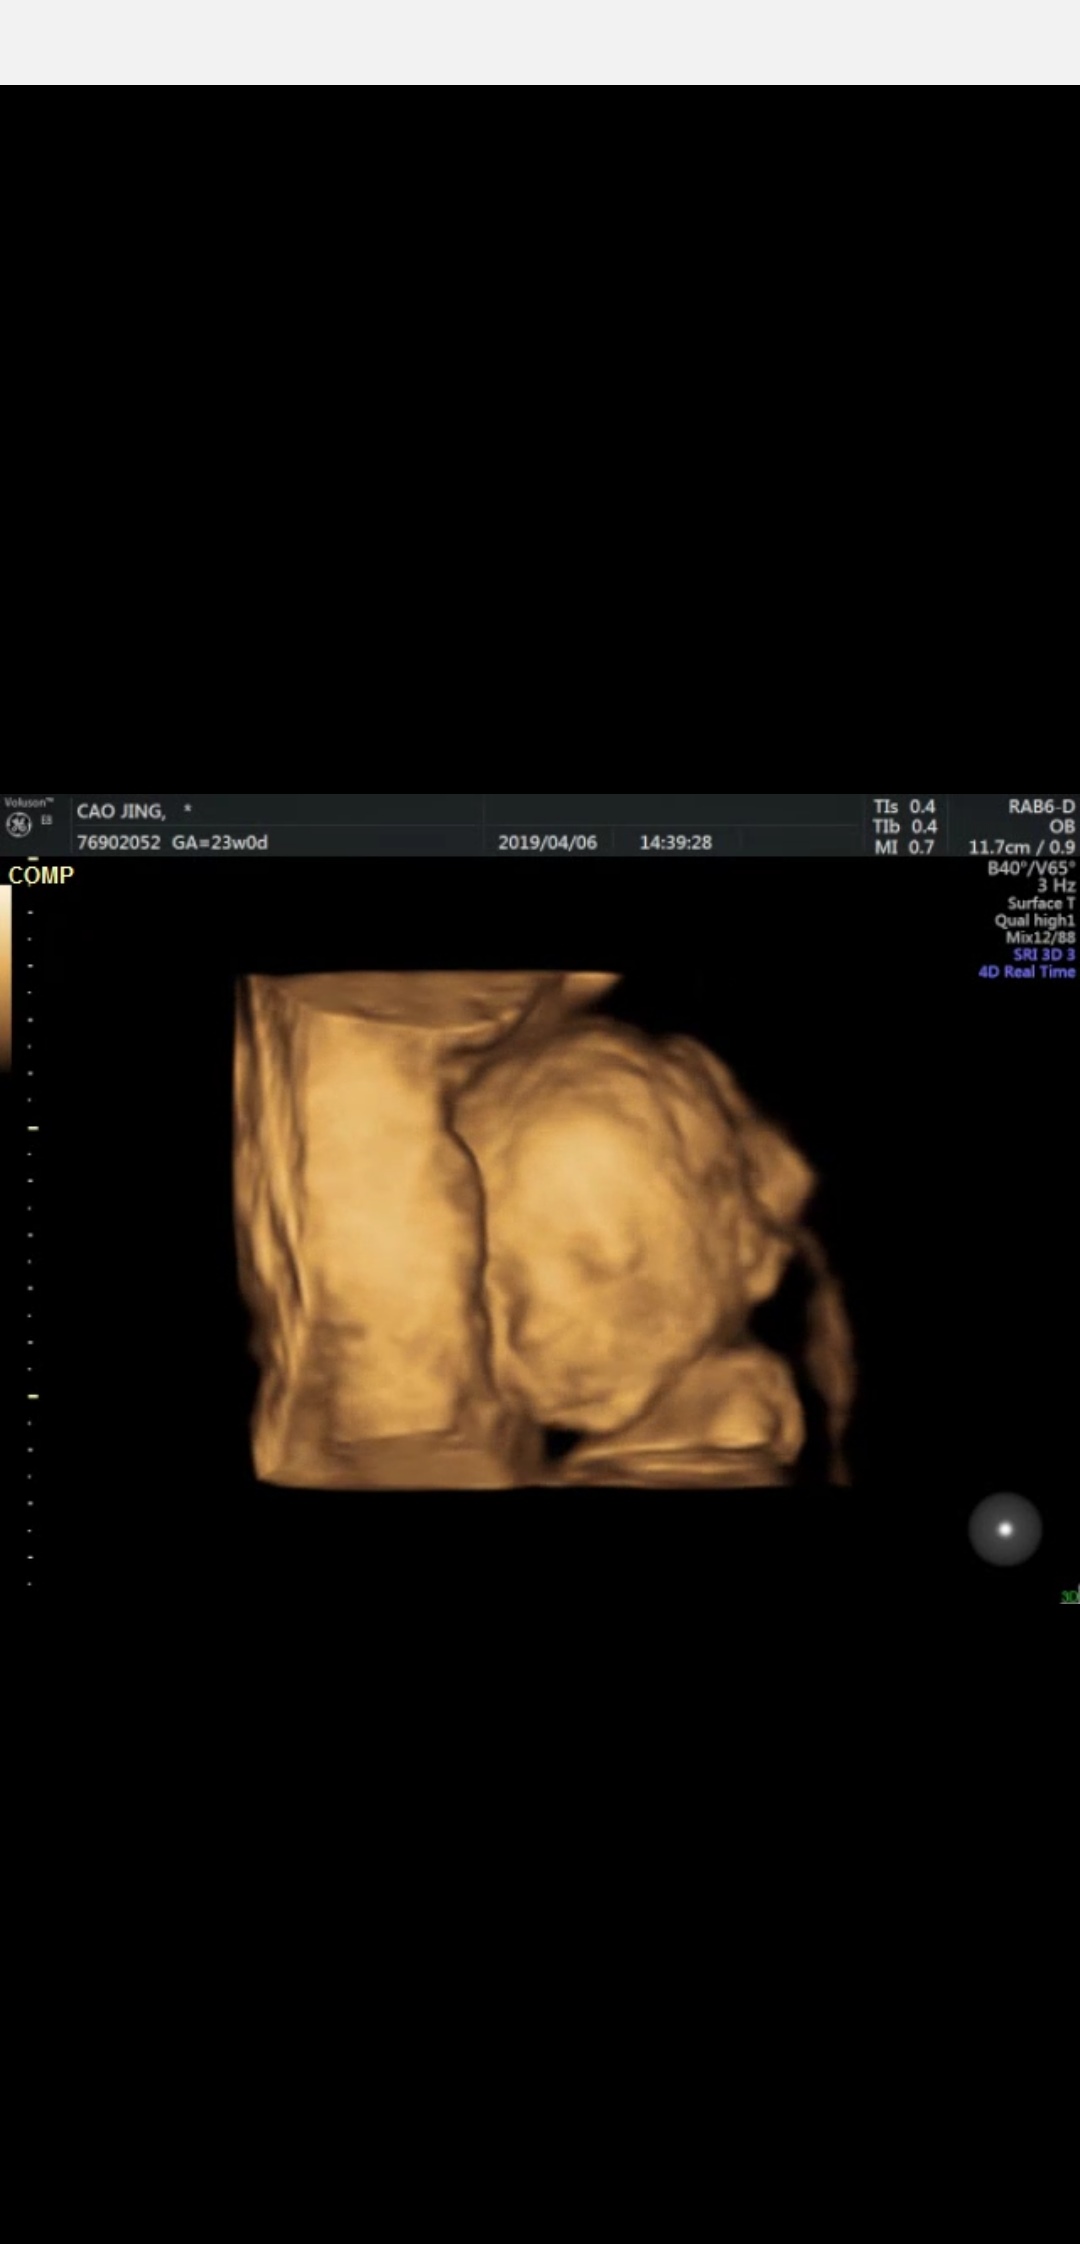

2019-04-07

4842 人回复